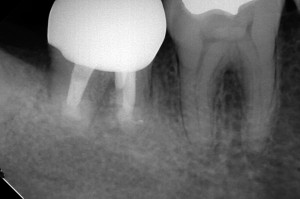

DB9747_150901140708(調整後)外科後

根尖の病巣は治ったが・・・

そう、分岐部から排膿してきてしまいました。

エンド的には成功でも、ルートトランクが浅くなると、歯周病で最も厄介な、分岐部病変になってしまうことが・・・

DB9747_151106115509(調整後)EMD後

排膿もなくなり、本当に良かった・・・透過像も心なしか良くなってきている。